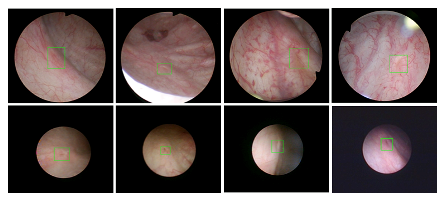

近年来,联合实验室发展了泌尿镜手术实时识别技术,人体姿态精确识别技术,另外围绕小儿先心病手术、肝癌消融手术、数字口腔诊疗的智能化提升等内容进行应用研发。